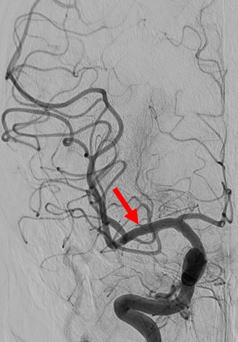

当院で行われた血栓除去術の実際の症例をお示しします。1例目は65歳男性、自宅にて動けなくなっているところを発見されました。軽度意識障害、重度の左片麻痺にて当院に救急搬送、NIHSS17点、心房細動を認めました。頭部MRI(図4)にて右大脳半球に矢印のように虚血巣の出現あり、MRA(図5)にて矢印のように右中大脳動脈の描出なく、緊急にて血管撮影を施行しました。バルーン付きのガイディングカテーテルを入れて、血栓より遠位にマイクロカテーテルを入れて、血栓の遠位からステント(Trevo provue 4×20mm)を展開後、血栓を回収しました。その後の撮影では閉塞していた血管はTICI2bまで再開通しており、治療直後から患者さんの左片麻痺は改善を認め、翌日のMRIでも梗塞巣は広範とならず、治療17日後に自宅退院しました。現在は社会復帰しており、元のお仕事にも戻っております。(図6、7、8、9参照)

図6:総頚動脈撮影の正面では青矢印の様に、右中大脳動脈が閉塞しています |